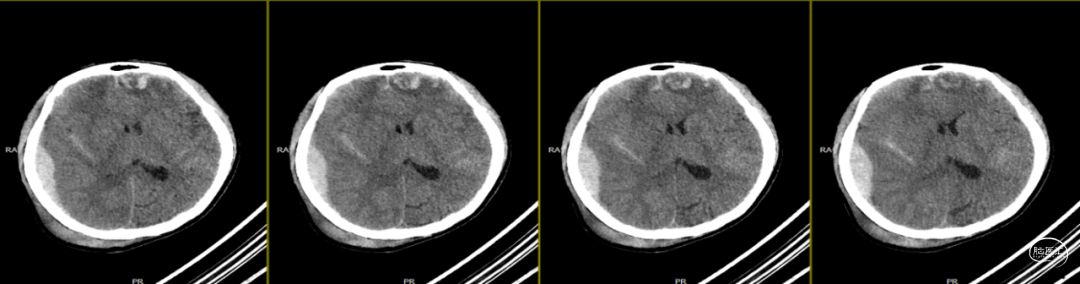

因患者局部头皮逐渐膨隆,且头皮疼痛,于术后89天再次入院。体查可触及头皮下异常物质存在,考虑头皮下积脓并硬膜外脓肿可能,患者无发热,血常规、C反应蛋白、降钙素原等感染指标均为在正常范围。

第1次术后88天,即第2次入院前1天复查(如上图),经反复沟通病情,病人及家属仍拒绝去除骨瓣清创手术,但同意进行手术清创。术中见右侧额部皮下炎性肉芽组织增生,伴有少量分泌物流出,骨瓣下见乳白色脓性分泌物,未闻及明显异味,收集脓性液体送细菌培养、涂片检查,局部硬膜增厚,较多炎性增生组织于局部硬脑膜黏连紧密,缓慢刮除局部异常增生组织后,低功率双极电凝行硬脑膜止血,骨瓣可见右侧额部外板局部被侵蚀,清理表面异物后,使用双氧水浸泡冲洗,并浸入碘伏液中消毒;彻底清除硬膜外、骨缘及右侧额部皮下增生异常组织,额顶部愈合不良刀口予以局部清创,反复使用双氧水及稀释后碘伏溶液冲洗创面,更换钛板及钛钉,还纳骨瓣并固定,皮下留置负压引流管1根,缝合逐层。术后使用万古霉素静脉抗炎治疗,留取术中脓性分泌物进行细菌培养及涂片检查(培养及检验均呈阴性)。

第2次术后第1天复查颅脑CT资料(第1次术后92天)(如上图)。